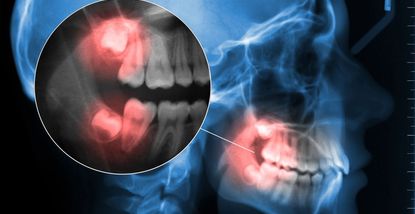

Proces All-on-4 terapije započinje detaljnom dijagnostikom – digitalnim 3D snimanjem i planiranjem položaja implantata pomoću specijaliziranog softvera. Nakon toga slijedi kirurški zahvat u kojem se ugrađuju četiri implantata u strateški raspoređene točke čeljusti.